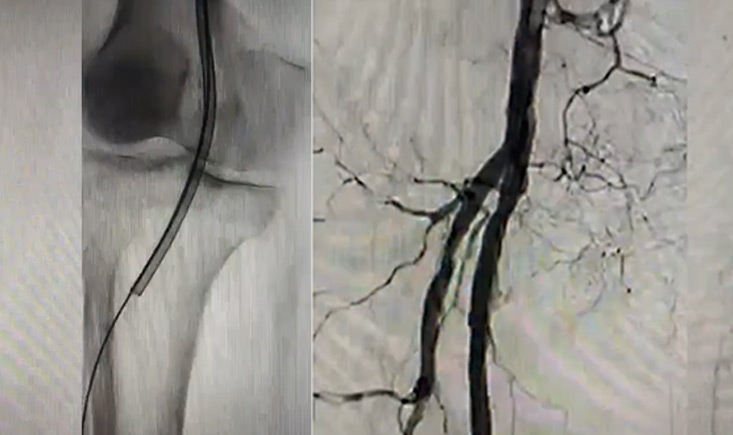

The session covers a range of topics, from the research regulations in New Zealand and the management of DVT in Singapore, to CFA treatment strategies in Japan and the handling of acute lower limb ischemia in Malaysia.

A focus on pulmonary embolism endovascular repair in India highlights innovative practices, while real-world data on the Ranger DCB in CLTI patients provide tangible insights into treatment outcomes. The session also explores aortic dissection management in China, showcasing the journey from traditional open surgery to cutting-edge endovascular solutions.